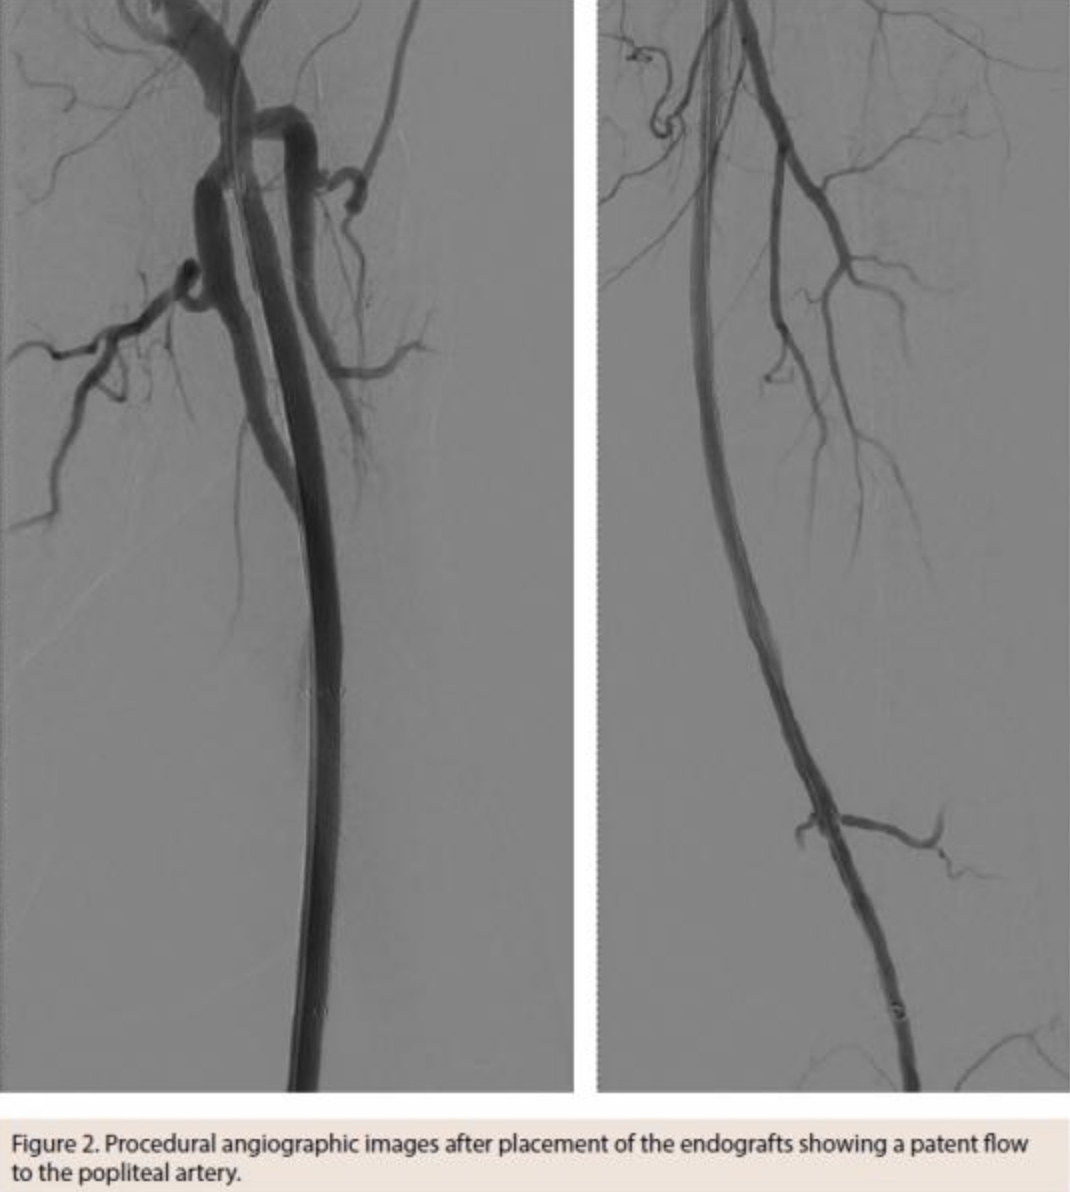

A 73-year-old male patient with a history of dyslipidemia, lower-back pain after a vertebral fracture, and nicotine abuse presented with a progressive and disabling intermittent claudication on the left side, not responding to prolonged supervised walking exercise. The patient had an ankle-brachial index of 0.68 and imaging studies showed an 18 cm-long occlusion of the superficial femoral artery (Figure 1). After recanalization, the lesion was treated with two percutaneously placed 6 mm Viabahn endoprostheses, covering the entire diseased segment (Figure 2). The postoperative course was uneventful, the ankle-brachial index normalized and the patient was discharged on the first postoperative day.